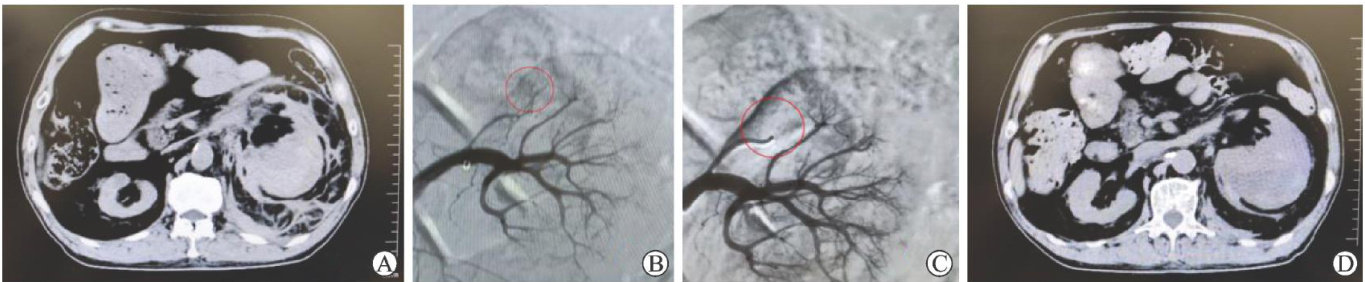

ABSTRACT:ObjectiveTo investigate the diagnosisand treatment of 2cases with spontaneous renal vascularrupture,and discussthe posiblecausesand treatment methods of thisdisease.MethodsTheclinicaldataand treatment methods of the 2 patients with spontaneousrenal vascularrupture treatedwithrenalarteryembolizationin Universal Global Xi'an Beihan Hospital were analyzed.Relevant literature was reviewed to summarize the posible causes of this condition.ResultsThe patientshad noobvious historyoftraumaandnoobviousabnormalcoagulationfunction,and soughttreatmentdueto sudden lumbarandabdominal pain.Laboratory tests revealed significantly decreased hemoglobin level,and elevatedblood glucose (27.8,27.6mmol/L) .Abdominal computed tomography(CT) indicated perirenal hematoma and active bleeding. The bleeding arteries were located attheterminal branchesof theanteriorrenalartery.Preciseembolization was performed using CTangiographyand selective renal arteryangiography plus embolization,achieving an immediate hemostasis sucess rate of 100% .Postoperative hemoglobin level stabilized,andfollow-up CTscansshowed significant absorptionoftheperirenal hematoma without significant deteriorationofrenalfunction.Basedonliteraturereviewandcaseanalysis,thepossblecauseof spontaneous renal vascular rupture in these two patients wasrenal vascularsclerosis due to long-term diabetes.Other common etiologiesof thiscondition included renal tumor,vascular malformation,and hypertension.ConclusionSpontaneous renal vascularruptureisrare.Renalarteryembolization,asaminimally invasive treatment,caneffectivelycontrolbleeding and protectrenal function.Thespecificpathogenesisofthisconditionstillrequires furtherinvestigation.Long-termdiabetes melitus with poor blood glucose control may be associated factors,but more evidence is needed.